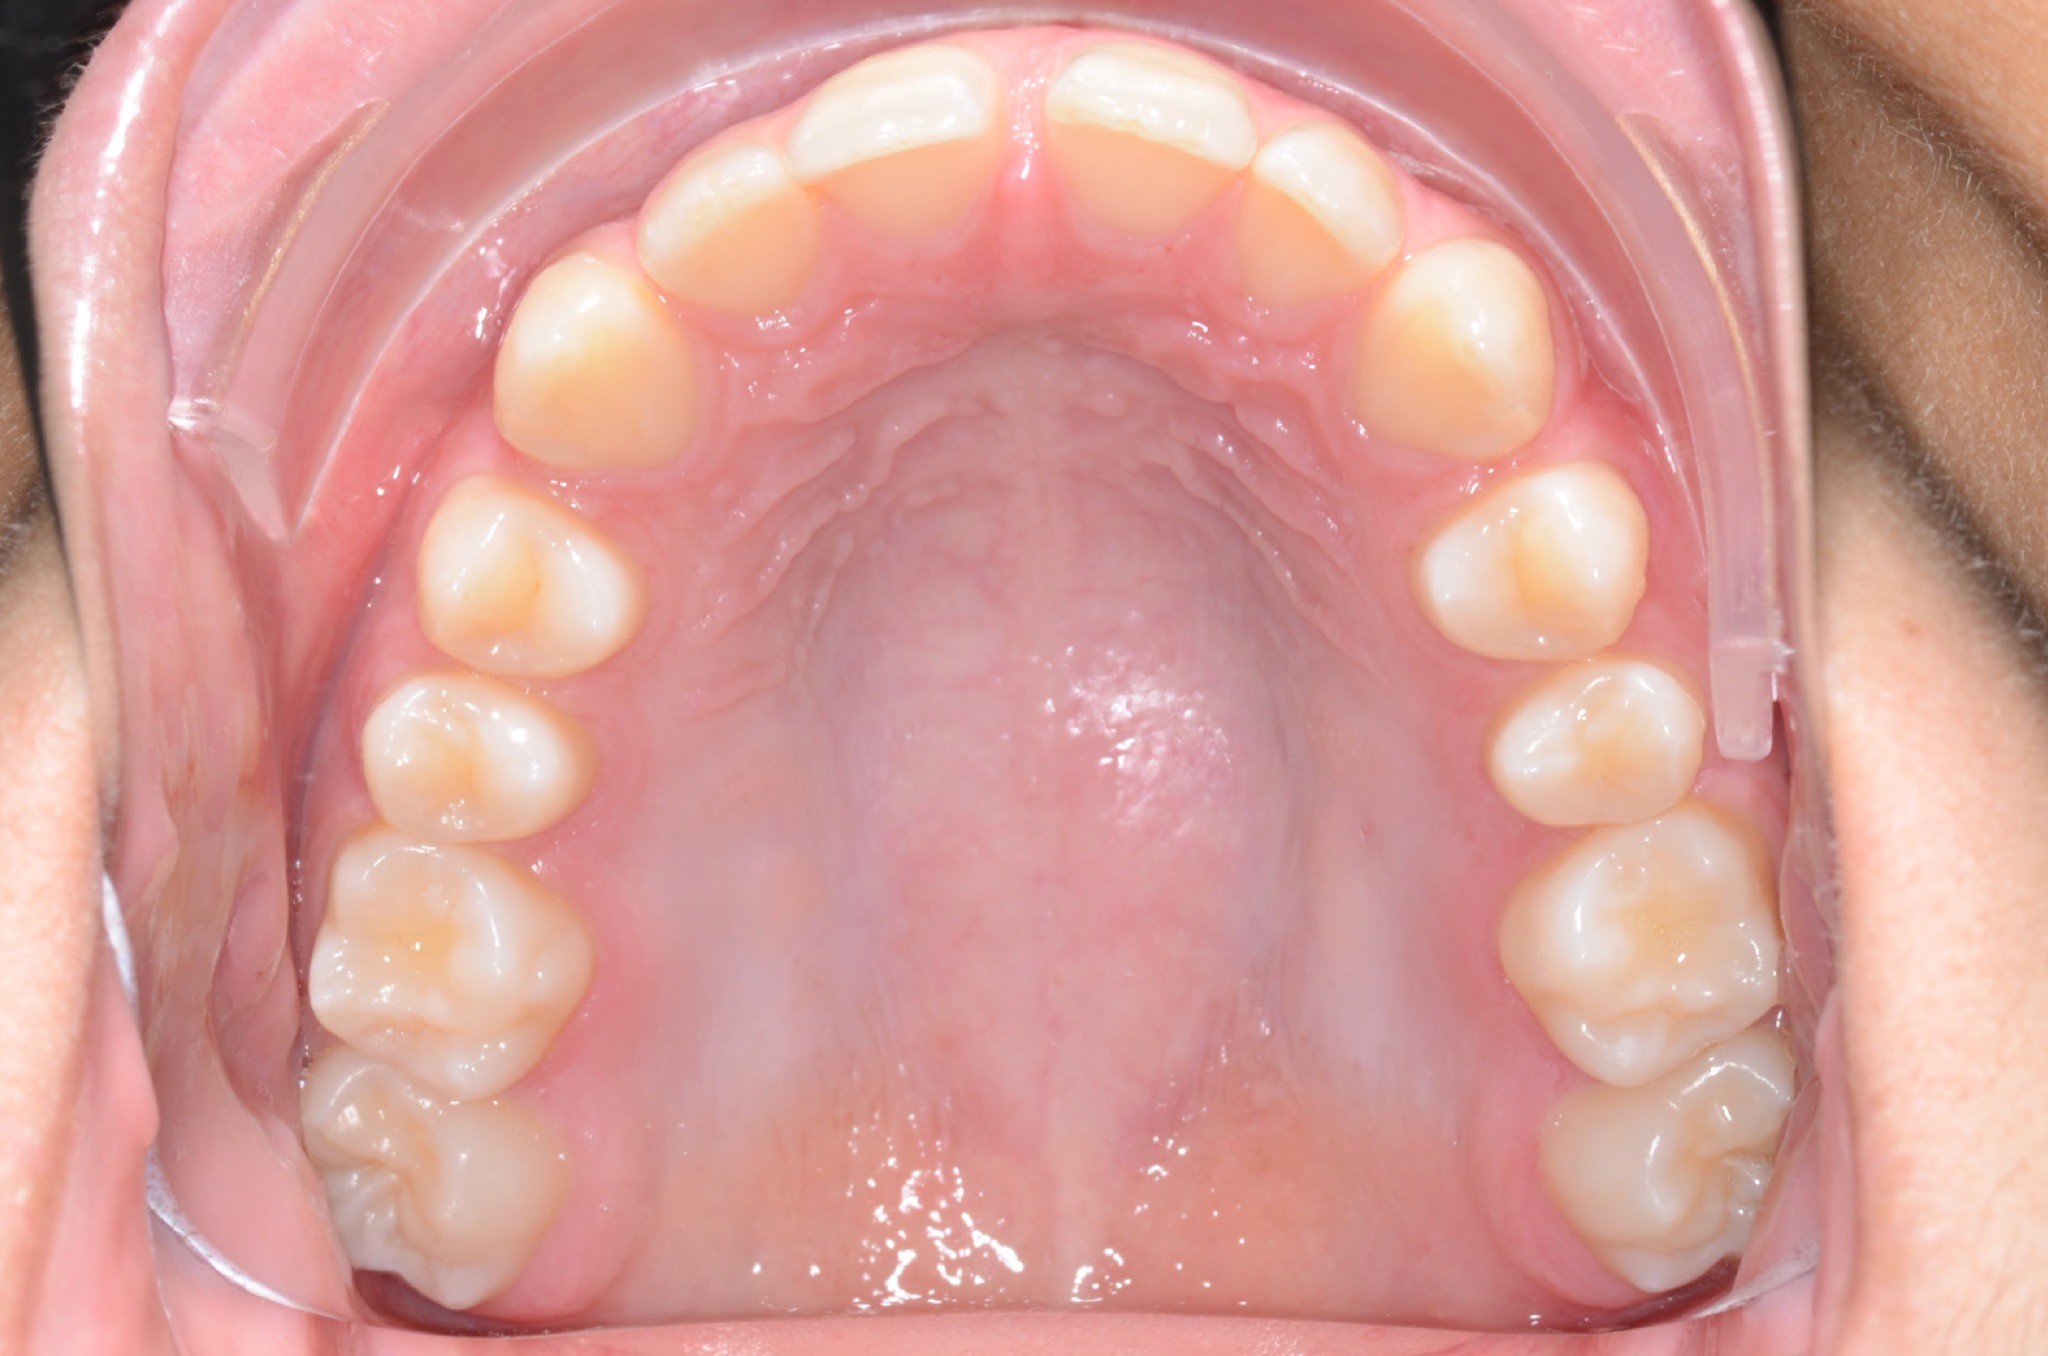

Initial treatment

INTRAORAL